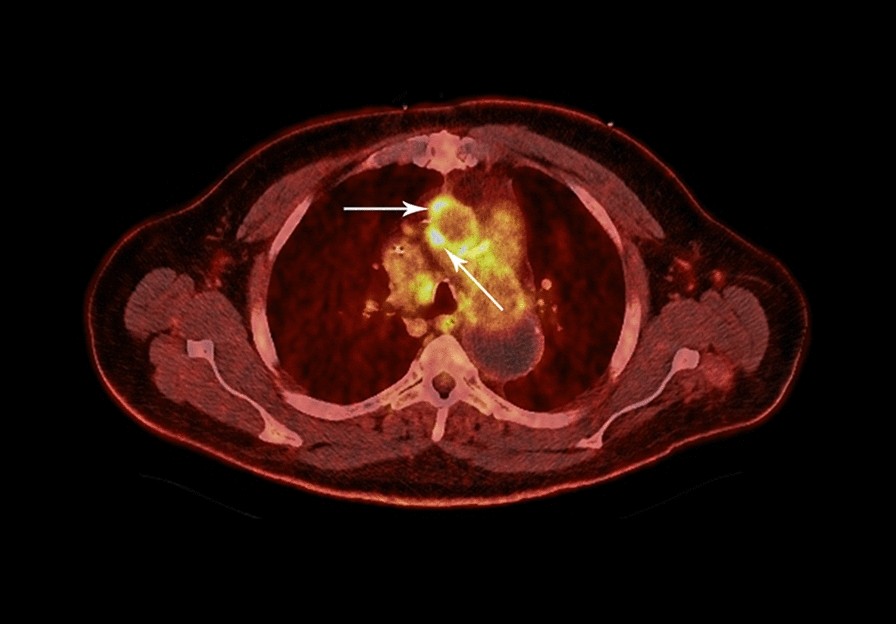

Fig. 3

From: An unusual case of Cardiobacterium valvarum causing aortic endograft infection and osteomyelitis

Positron emission tomography–computed tomography (PET/CT) of the chest. Hypermetabolic soft tissue (arrows) along the right lateral and anterior aspect of the ascending aortic endograft with a maximum standardized uptake value of 9.4, suspicious for aortic endograft infection